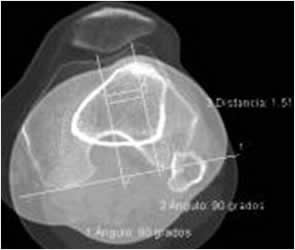

Distancia tuberosidad tibial/surco femoral (TA/GT: Tuberosidad anterior/Garganta troclear).

Medido mediante TAC, con rotación lateral de los pies de 15º. Se realizan cortes superpuestos sobre la mitad de la patela y que pase por los cóndilos femorales y otro en la tibia proximal, a nivel de la tuberosidad. (1, 3). El estudio se realiza en reposo y con contracción de los cuádriceps y flexión de 15º en las rodillas, utilizando un soporte. (22). (Fig 86).

Se traza una línea tangencial que pase por la parte posterior de los cóndilo femorales y de allí una perpendicular, que cruce por la parte mas profunda o el centro del surco troclear. (Línea del surco). La otra es una paralela a la línea del surco y que pasa por la parte mas alta de la tuberosidad tibial. (Línea de la tuberosidad tibial). (1, 3, 18).

Se mide la distancia entre la línea del surco y la de la tuberosidad de la tibia, que tiene un rango entre 7 y 17 mm y un promedio de 15 mm. (3, 18). Aumenta en la luxación recidivante de la rotula, inestabilidad patelar y artrosis patelofemoral, siendo mayor de 20 mm. (3). (Fig 84 y 85).

Fig 84. TA-GT.

A: TAC axial. Línea perpendicular a la bicondilea posterior y que pasa por la parte mas profunda de la garganta troclear.

B: TAC axial. Línea paralela a la del surco, que cruza por la parte mas alta de la tuberosidad tibial.

Se superponen y se mide la distancia entre la linea del surco y la linea de la tuberosidad tibial.

Fig 85. TA-GT.

Medición del ángulo con el software de la máquina, con una distancia de 15 mm.